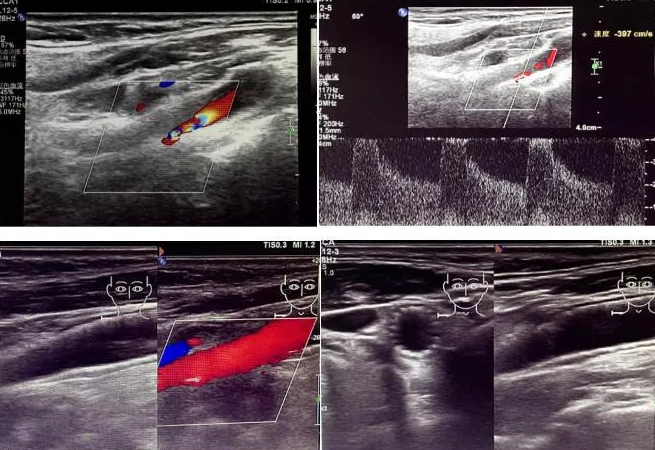

該患者因反復(fù)頭暈前來(lái)國(guó)文醫(yī)院就診。經(jīng)醫(yī)院超聲科運(yùn)用高端超聲設(shè)備進(jìn)行頸動(dòng)脈超聲檢查后發(fā)現(xiàn),其右側(cè)頸動(dòng)脈狹窄程度超過(guò) 90%。如此嚴(yán)重的狹窄狀況,猶如高速公路上的嚴(yán)重堵車(chē),使得血液流通受阻,大大增加了腦梗死的風(fēng)險(xiǎn),時(shí)刻威脅著患者的生命安全。

頸動(dòng)脈超聲檢查作為一種無(wú)創(chuàng)、安全且準(zhǔn)確的篩查手段,在評(píng)估血管健康狀況方面發(fā)揮著重要作用。它能夠清晰地顯示血管的狹窄程度以及斑塊性質(zhì),為臨床診療提供可靠的依據(jù)。國(guó)文醫(yī)院超聲科配備的高端超聲設(shè)備,更為精準(zhǔn)診斷提供了有力支持。